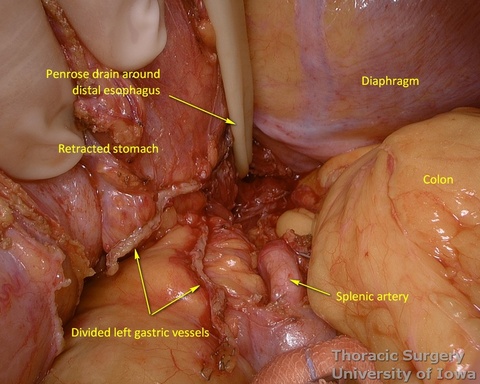

- The abdominal esophagus, periesophageal fat, and nodes are dissected and encircled with a Penrose drain for retraction.

- Peritoneum is incised, protecting the splenic artery and pancreas. 1-2 mm posterior gastric artery, originating from the proximal splenic artery fs present (in half of individuals) and is divided.

- Once the stomach is mobilized and reflected anteriorly, the left gastric vascular pedicle is identified and dissected close to the origin for adequate lymphadenectomy. Care is taken to not injure splenic artery and pancreas.

- Left gastric vessels are divided with an endoscopic linear cutting stapler proximally, including all adjacent lymph nodes in the specimen.